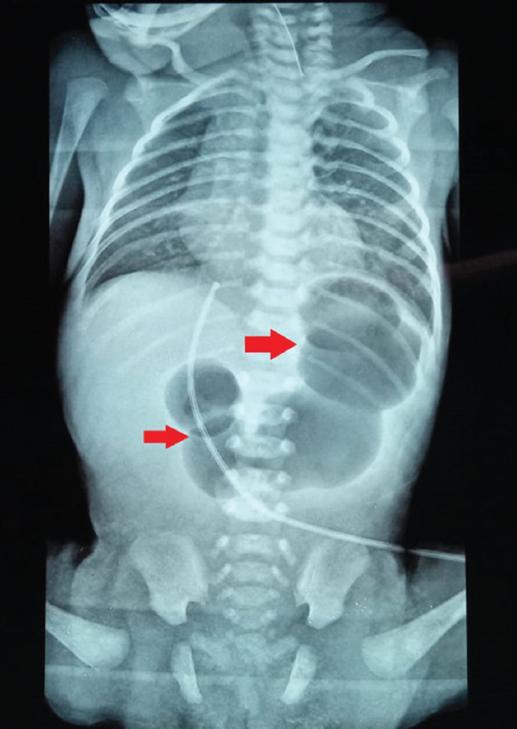

Se coloca en cuna radiante a 37 °C con oxígeno libre a 2 l/min. En la exploración se encuentra permeabilidad de coanas, reflejos primitivos presentes, tórax y abdomen sin compromisos, cadera estable, llenado capilar de 3 segundos, fontanela anterior de 1 cm aproximadamente y posterior parcialmente cerrada; no se encuentra fosa anal (Fig. 1) y existe impedimento para el paso de la sonda orogástrica. Se realiza una radiografía toracoabdominal anteroposterior que evidencia una imagen característica en cuádruple burbuja y ausencia de aire distal, que hace sospechar atresia intestinal (Fig. 2). Ante estas alteraciones, se decide trasladar a la paciente a nuestra institución pública.

Se solicita invertograma para determinar la altura del cabo colónico; sin embargo, la probable presencia de atresia duodenal o yeyunal no permite una correcta valoración (Fig. 3). La búsqueda de células meconiales en orina fue negativa.